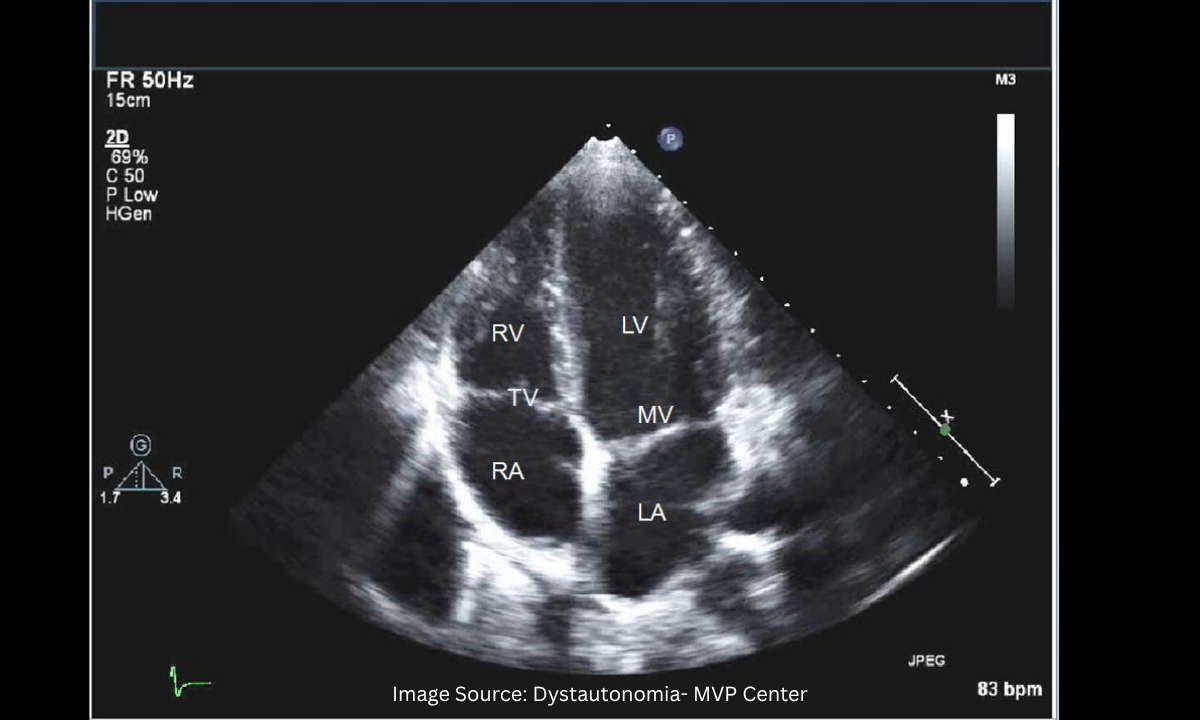

Following an abnormal ECG, patients frequently ask about scheduling an echocardiogram to evaluate heart blockage. An echocardiogram utilizes high-frequency sound waves to create a live, moving video of your heart. Here is what it looks like:

It allows our specialists to view the physical structure of your heart valves and measure exactly how forcefully your heart muscle pumps blood with every single beat.